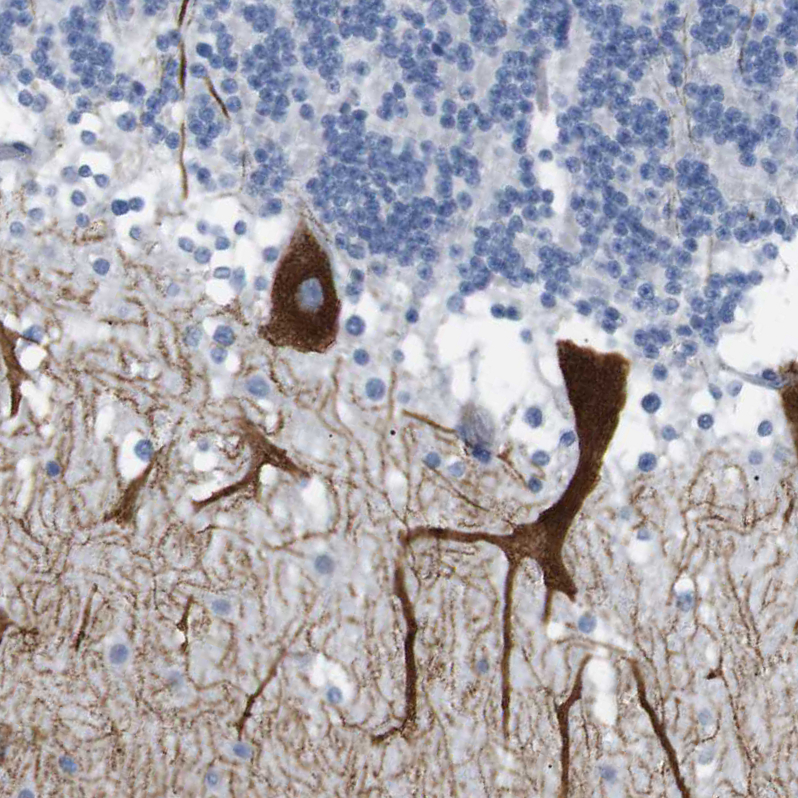

Immunohistochemical staining of human cerebral cortex shows weak to moderate cytoplasmic positivity in neurons.